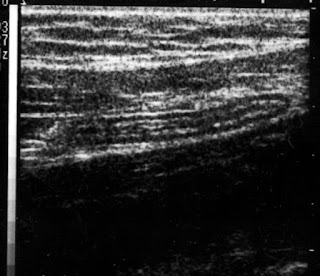

ecografie apendicita

galerie foto ecografii

imagini